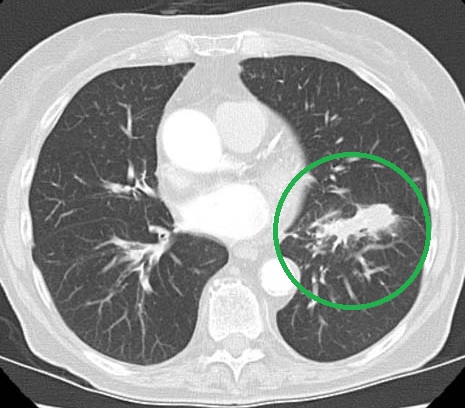

Березень 2009 Грудень 2009

Комп’ютерна томографія: зменшення пухлини у пацієнтки з недрібноклітинним раком легені.

Пацієнтка не приймала хіміотерапію і регулярно пила канадський чай «Ессіак».[5]

Дослідники з Університету Торонто (Онтаріо, Канада) і клініки радіологічної онкології Лікарні Принцеси Маргарет (Онтаріо, Канада) д-р Gladwish і д-р Clarke описали випадок зменшення пухлини легені і скорочення пухлинного ураження лімфовузлів середостіння у пацієнтки, яка не отримувала хіміотерапію, а регулярно приймала тільки чай «Ессіак». Звіт про цей унікальний випадок був опублікований в 2010 році у British Medical Journal [5]